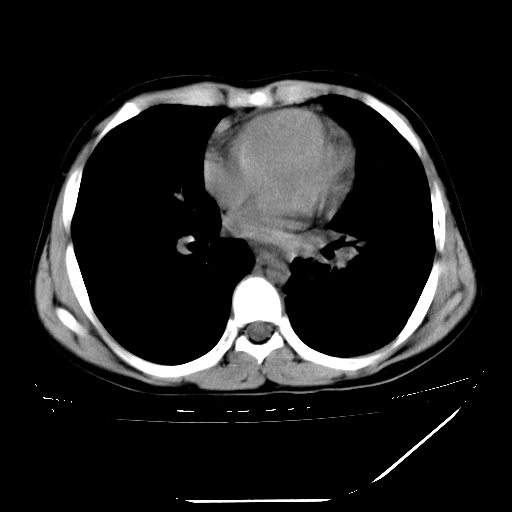

男,13岁,咳嗽、咳痰伴发热一周。

上纵隔课件多枚淋巴结,部分相互融合,左侧支气管壁增厚,肺纹理较右侧增粗,患者,男,13岁,

中上纵隔见多枚淋巴结肿大,部分相互融合成团片,左肺门增大,上叶支气管变窄,肺内多处斑片状 索条状及棉絮状致密影。临床“男,13岁,咳嗽、咳痰伴发热一周。”首先考虑:原发综合征!不除外淋巴瘤可能!

纵隔多发肿大淋巴结,部份有融合改变。双肺血管气管束增厚,以肺门为中心向外周散发,以左肺下叶为明显。考虑淋巴瘤可能性大。不除外原发综合征。

中上纵隔见多枚淋巴结肿大,部分相互融合成团片,左肺门增大,上叶支气管变窄,左肺支气管血管束增粗,可见磨玻璃样影。临床“男,13岁,咳嗽、咳痰伴发热一周。”首先考虑:淋巴瘤可能性大!